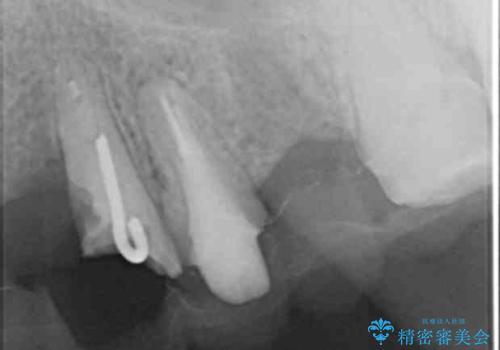

歯を牽引し健全歯質を歯肉縁上まで引き上げ、歯の保存を試みることにしました。

歯の牽引後、ブリッジの仮歯で保定しながら歯肉・骨の治癒を待ったのち、ブリッジによる補綴を行いました。

根の長さが短くなるためブリッジの支台歯としては弱いこと、長期的予後は不明なことをご理解頂いた上で治療を行いました。

根管治療はご希望されず行っておりません。